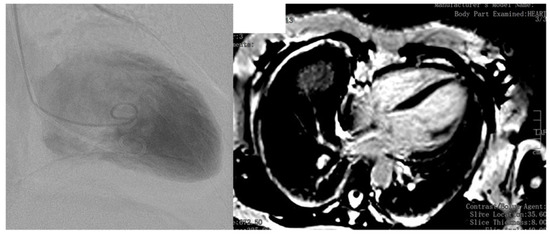

4. Case Report